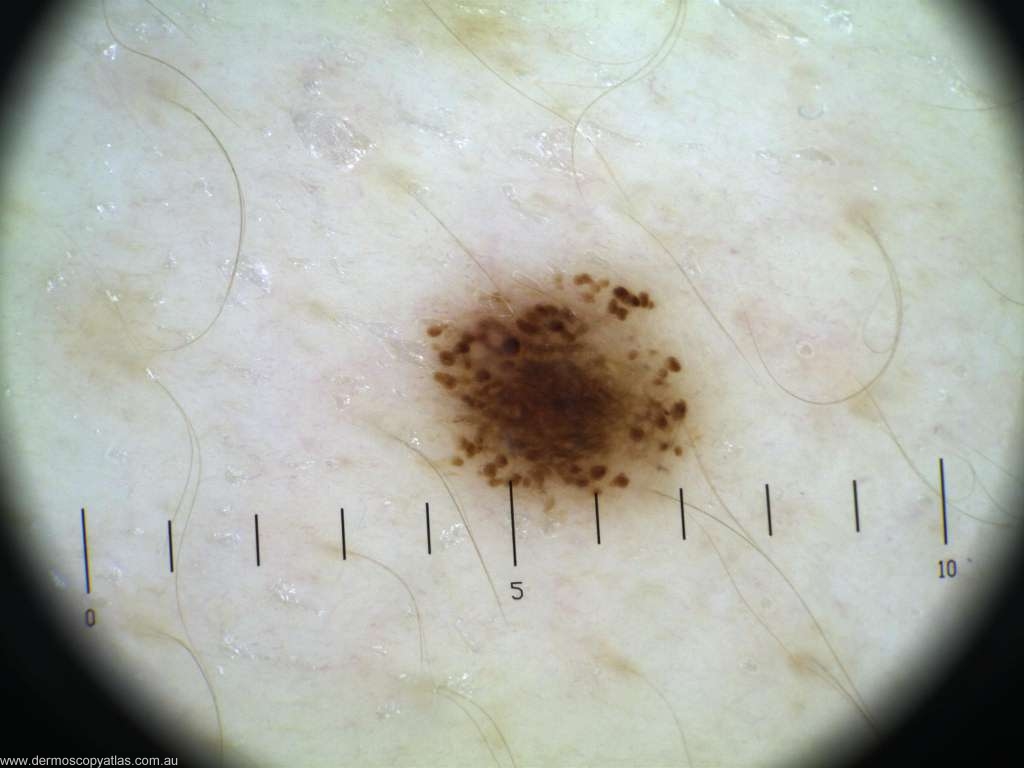

Case 10 Female aged 49. Routine check. No history. R lateral breast-axilla

Question: What is your diagnosis? Consider Melanoma in situ, Invasive melanoma,Solar lentigo, Benign nevus and dysplastic nevus.

Answer: Histology: Mildly atypical compound naevus